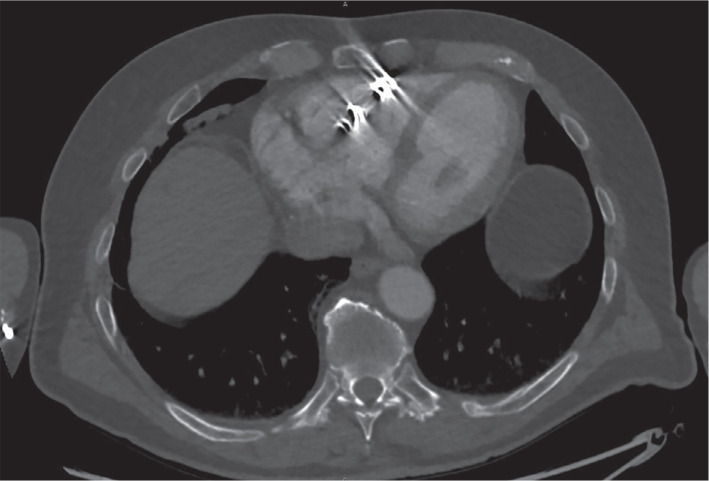

Leadless pacemakers (LPs) are emerging options for bradyarrhythmias. However, extraction can be risky if the device is in an unfavorable position. We present a challenging case of a Nanostim LP (NLP) (Abbott Medical Inc., Abbott Park, IL, USA) placed 8 years prior to removal and subsequent replacement with an AVEIR LP (ALP) (Abbott). A 72-year-old man received an NLP in 2015 for persistent atrial fibrillation with bradycardia. The NLP could not be interrogated in our office. An external event monitor demonstrated persistent atrial fibrillation with bradycardia and pauses. A premature battery depletion of the NLP was suspected. An ALP was chosen for replacement. On a computed tomography scan of the chest, the NLP was seen in the mid-free wall of the right ventricle, and its proximal portion abutted the tricuspid annulus. The AVEIR retrieval catheter (ARC) was used for retrieval. Multiple attempts were made to snare the device, yet it proved difficult due to poor placement and button tissue formation. The snare became damaged, and a second ARC was needed. On the successful attempt, the NLP was snared proximally and permitted docking. We advanced the protective sleeve over the NLP body, but resistance was observed due to tissue growth. Counterclockwise torsion was applied, and the device disconnected. Once the NLP was in linear orientation, the protective sleeve was eventually positioned over its body, allowing removal. The ALP was then installed without difficulty or structural complications. This report shows the importance of proper LP placement in the right ventricular septal wall. LP removal can be performed safely, yet complications can arise based on the age and location of the LP. The ARC can be successfully used to extract non-AVEIR LPs with evidence of docking button tissue growth. Similar interventions should exercise caution when attempting extraction and subsequent implantation.